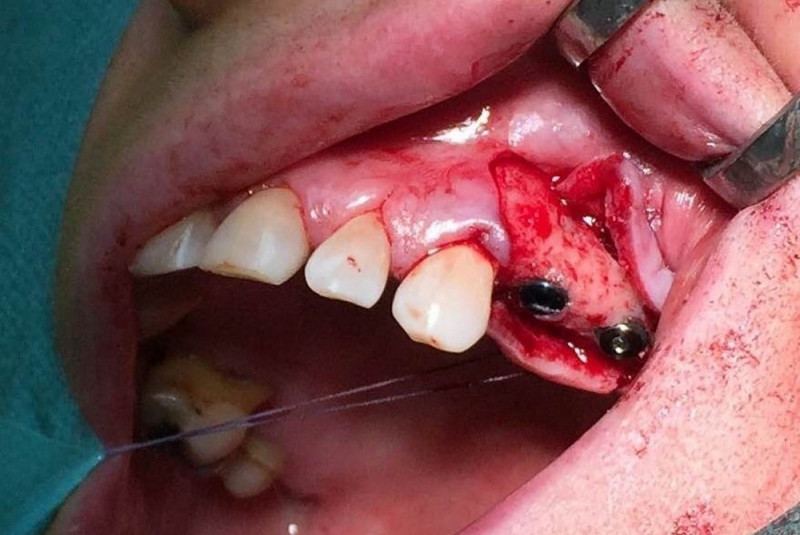

- Implantológia:

1. nadstavba kosti augmentačnými materiálmi (umelé kostné tkanivo, sinus lift a pod.)

2. implantológia, vrátane 3D - dentálneho CT